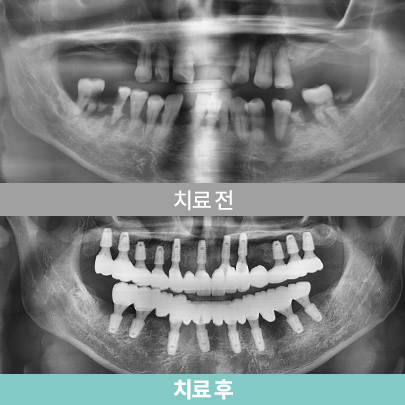

전악 임플란트

치아가 하나도 없거나 심각한 구강질환을 앓고 있어도

전악 보철을 제작, 임플란트를 치조골에 식립해

기능적, 심미적으로 자연치아와 가장 유사한 수준으로 재현이 가능합니다.